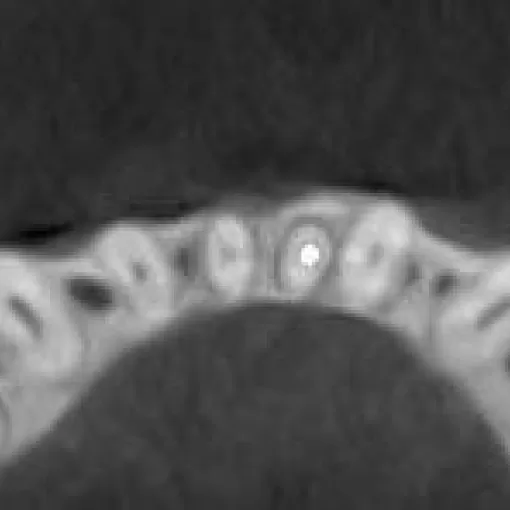

Пациент обратился с целью имплантации в области отсутствующего зуба 4.6. Однако после КЛКТ (3Д) исследования был обнаружен воспалительный процесс (киста) в области соседнего зуба 4.7 (рис. 1).